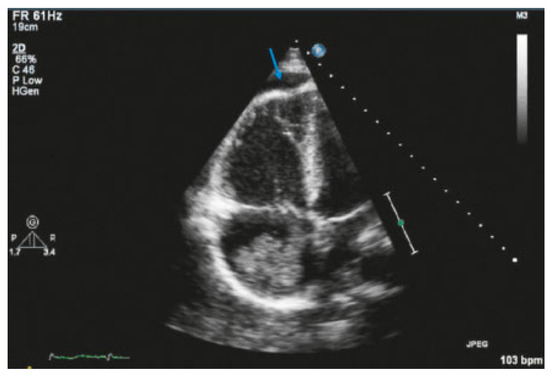

Value of Echocardiography in Differentiation of Acute Dyspnoea

by Ioannis Kapos and Felix C. Tanner

Echocardiography is one of the most effective imaging modalities for investigation of patients with acute dyspnoea. This review summarises appropriateness criteria and current guidelines for the use of cardiac ultrasound in common clinical scenarios presenting with acute dyspnoea, and illustrates such scenarios with [...] Read more.

Echocardiography is one of the most effective imaging modalities for investigation of patients with acute dyspnoea. This review summarises appropriateness criteria and current guidelines for the use of cardiac ultrasound in common clinical scenarios presenting with acute dyspnoea, and illustrates such scenarios with typical echocardiographic findings. Full article

Show Figures

Figure 1